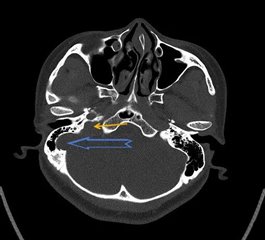

颈静脉球高位:颈静脉球位于岩骨下方的颈静脉窝内,是颅内乙状窦和颈内静脉连接处的球形膨大。颈静脉球高位是较为常见的解剖异常,发生率约25%,大多数没有临床症状也无需特殊处理。

在正常的CT图像上耳蜗基底转的层面是看不颈静脉球的;当颈静脉球顶部超过耳蜗基底圈下缘或鼓室下缘,或突入中耳腔时,称为高位。

乙状窦前位+乙状窦憩室+颈静脉球高位(黄色箭头)